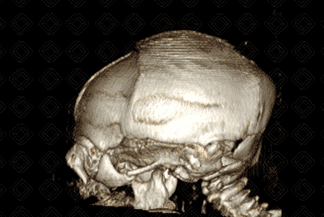

• Na última imagem, reconstrução tridimensional (3D) do mesmo paciente confirma a microcefalia e evidencia o cavalgamento das suturas coronais e a perda do ângulo frontonasal.

• Tomografia computadoriza do crânio : No zika vírus, alguns achados tomográficos podem auxiliar a confirmar a suspeição clínica, como: microcefalia; protuberância de pele na região occipital externa; redução do ângulo frontonasal; excesso de pele na região occipital; cavalgamento de suturas; fechamento precoce da fontanela anterior; distúrbio de migração neuronal; atrofia cerebral difusa; calcificações. Padrão das calcificações: costumam distribuir-se na transição do córtex com a substância branca (região corticossubcortical) e, menos comumente, nos núcleos da base e tálamos;